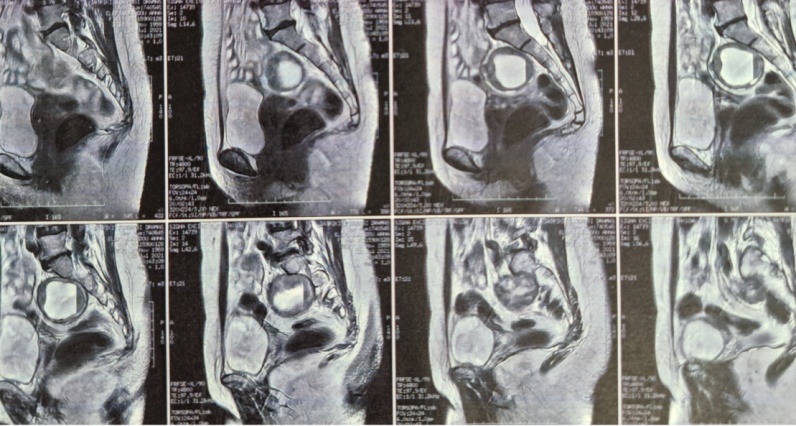

Both cystadenomas were excised with preservation of both ovaries (Courtesy Dr. V. Penopoulos)